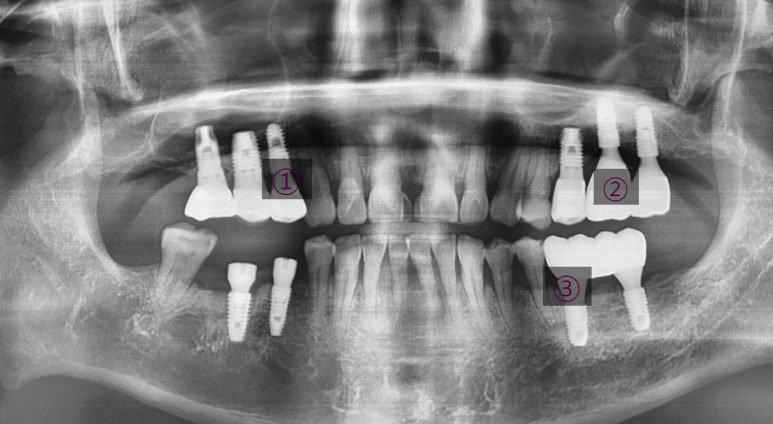

다른치과에서 몇년전에 한 인플란트가 흔들리고 붓는다고 온 분이었습니다.

그림에 1로 표시한 부분은 임플란트 주변을 감싸는 뼈가 많이 녹아서 흔들리고

2로 표시한 치아는 중간 연결고리나사가 부러져서 임플란트 머리도 같이 흔들리는 상태였습니다.

1과 2 임플란트 모두 제거하고

새로 임플란트를 심어 완성하였습니다.